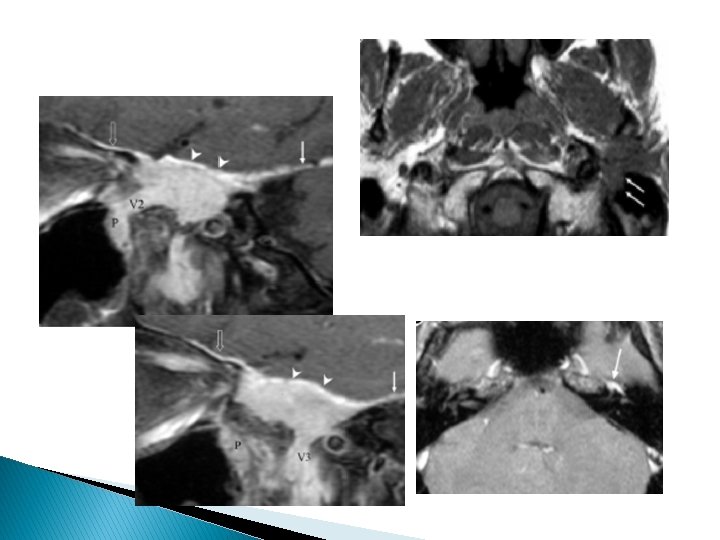

Infiltrations périneurales Tous les territoires innervés par le facial et ses branches collatérales sont à explorer lors du bilan d’une paralysie faciale persistante.

Difficulté de l’imagerie : trajet long (+++) du NF exocrânien + ses branches terminales ◦ Supérieure temporo-faciale ◦ Inférieure cervico-faciale

Les différentes anastomoses nerveuses du facial expliquent la diffusion périneurale de proche en proche pouvant en imposer pour une atteinte de la base du crâne ou une méningo-radiculite métastatique A : VII et V 2 par Nf grand pétreux (FPP) ; B : VII et V 3 par la corde du tympan et Nf petit pétreux ; C : VII et IX par l’anse de Haller (en dedans du trou stylomastoïdien ; D : VII et X (fosse jugulaire)